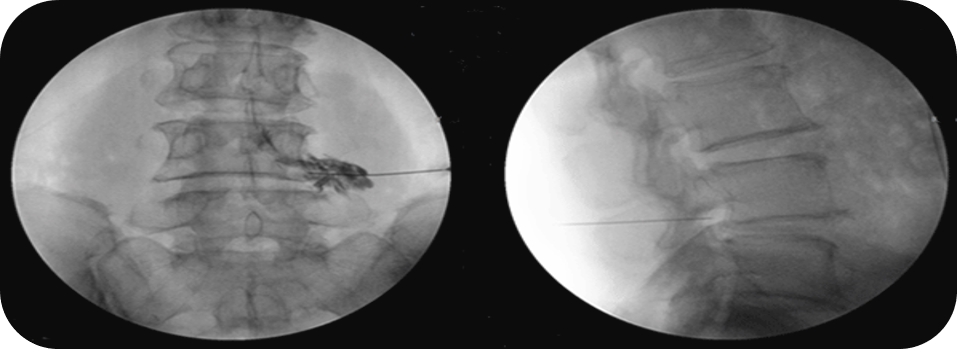

신경차단술은 목과 허리의 통증, 디스크성 통증 완화에 효과적인 비수술 치료법으로, 방사선 투시장비(C-arm)를 이용하여 척수신경을 둘러싸고 있는 경막의 바깥쪽에 약물을 주사하여 신경근 주위의 부종과 염증을 제거하고 통증을 개선합니다. 신경차단술이라는 이름 때문에 신경의 기능을 상실시키거나 마비시키는 것으로 오해할 수 있는데, 질환으로 인해 예민해진 신경을 정상으로 돌아오게 하거나 디스크 등에 의해 부어있는 신경의 부기를 제거하여 통증을 완화시키는 치료법으로, 수술로 통증을 완화시키기 어려운 척추 통증 등에 효과적입니다.

▲ 방사선 투시장비(C-arm) 영상